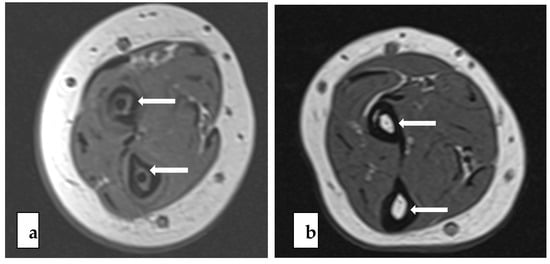

The PLGA implants of the BIN group were completely absorbed in 15 out of 26 bones (58%, 95% CI 37% to 77%) and almost completely absorbed in 11 bones, according to the MR images. The nail residuals appeared as faint, linear, low-signal short markings (Figure 2). The nail canal disappeared completely in 20 (77%, 95% CI 56% to 91%) forearm bones and almost completely in six bones. These residual canals demonstrated higher signals than the cancellous bone in the T1 and T2 images of the MRI. In two out of all 26 bones, thin nail residuals were found to be surrounded by a 3–4 mm halo effect (Figure 3). The tri-calcium-phosphate marker at the end of the nail was visible in 24 out of 26 (92%, 95% CI 76% to 98%) forearm bones in the MR images. (Table 3) The formation of intraosseal cysts was not detected.

Figure 3. T1-weighted (a) and T2-weighted (b) axial images with bright halo (white arrow) surrounding a faint residual of BIN in radial bone.

We found that the fatty intramedullary canal had been remodelled at the long-term follow-up. In six bones, some parts of the nail canals were still visible. These residual canals demonstrated higher signal than the cancellous bone in the T1 and T2 images of the MRI. In two out of all 26 bones, thin nail residuals were found to be surrounded by a 3–4 mm halo effect (Figure 3). This is in agreement with the literature, while Pihlajamäki et al. [34] previously reported a rim of a 1–2 mm halo around the PLLA implants that was bright in the T2, PD, and fat-saturated images. The clinical importance of the halo effect is not well understood but it will probably gradually disappear with time upon the continuation of tissue turnover.